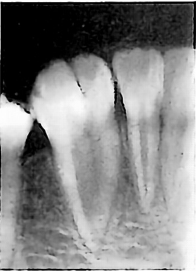

下图所示典型X线病变为

A.

牙中牙

B.

融合牙

C.

阻生牙

D.

畸形中央尖

E.

牙骨质结构不良